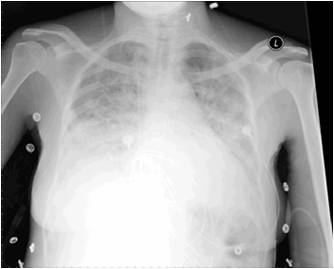

Los técnicos que vieron esta RX no advirtieron la existencia de un tutor metálico            que habia quedado en el torax atentos a la patología de base.